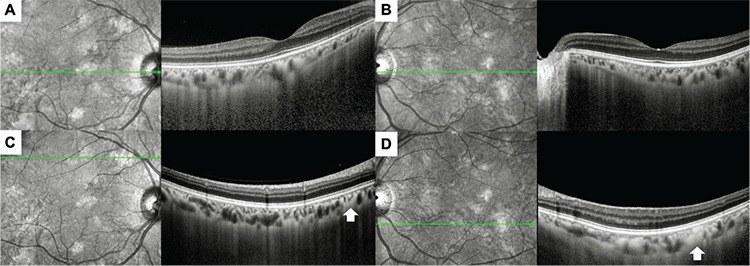

Objectives: Yasunari nodules are choroidal lesions observed in patients diagnosed with neurofibromatosis type 1 (NF-1) and characterized by relatively irregular dome-shaped, plaque-like, or patchy boundaries. The present study examines the multimodal imaging characteristics of Yasunari nodules and their value in the diagnosis of NF-1.

Materials and methods: Medical records including optical coherence tomography (OCT), enhanced depth imaging OCT, infrared reflectance (IR) imaging, OCT angiography, and color fundus images of NF-1 patients who were examined at the Department of Ophthalmology in Dokuz Eylül University Faculty of Medicine between January 2022 and December 2023 were retrospectively reviewed for the presence of Yasunari nodules.

Results: A total of 54 eyes of 27 patients were included in the study. At least one choroidal nodule was detected on IR imaging in 52 eyes (96.3%). In 31 (72.1%) of the 43 eyes (79.6%) with available high-quality OCT angiography images, choroidal nodules were observed as areas showing a flow deficit in the choriocapillaris layer. Of the total 54 eyes included, Lisch nodules without choroidal nodules were observed in 2 eyes (3.7%). In 16 eyes (29.6%), Lisch nodules were not detected despite the presence of choroidal nodules. Both Lisch nodules and choroidal nodules were detected in the other 36 eyes (66.7%).

Conclusion: Yasunari nodules are frequently observed in NF-1 cases and can be easily detected with multimodal imaging techniques, especially IR imaging. The ability to visualize choroidal nodules before the appearance of Lisch nodules demonstrates the importance of Yasunari nodules in the diagnosis of NF-1.